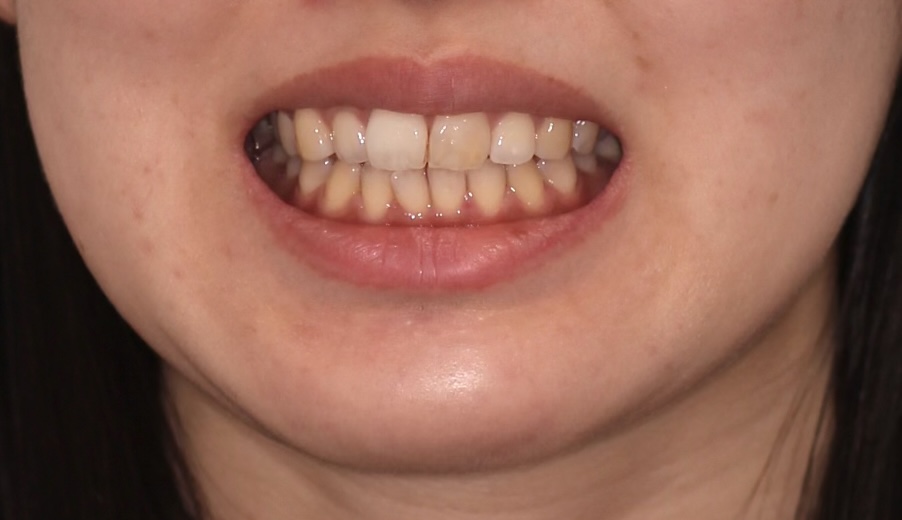

30代女性の患者様です。「歯並びを整えたい」というご希望に加え、「歯の色も白くして、お顔全体の印象を明るくしたい」という審美的なお悩みをお 持ちでした。 マウスピース型矯正(クリアコレクト)による歯列矯正と、ホワイトニングを組み合わせることで、健康的で美しいスマイルラインを実現しました。

2. Before / After(画像)

口元の変化: 歯並びが整ったことで、下顔面(口元)のバランスが改善され、より洗練された印象になりました。